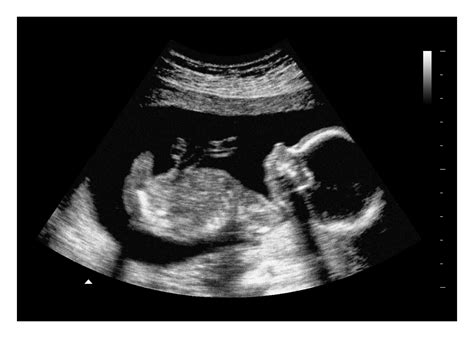

This image is a representation of what you might see during your 20 week ultrasound. The detailed scan provides a clear view of the baby's anatomy, allowing healthcare providers to assess development and identify any potential issues.

The 20 week ultrasound is a comprehensive scan that provides valuable insights into the baby's health and development. It is an important milestone in prenatal care and an emotional experience for many parents.